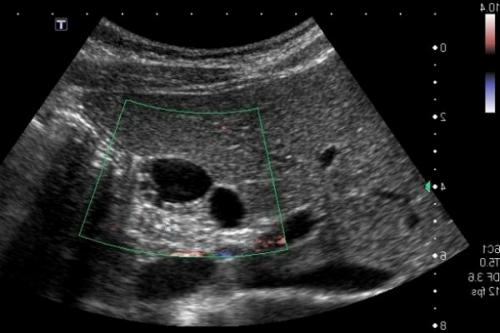

| Киста | Мягкая, капсула нормальной эхогенности, внутри жидкость | Округлое образование со светло-серой оболочкой, черной полостью |